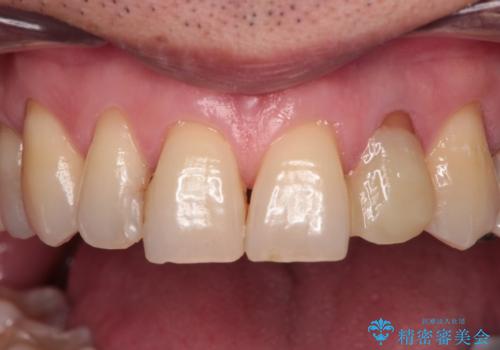

根管治療の土台のまま放置してしまった前歯 オールセラミッククラウンによる補綴治療

- 前歯の根管治療の際に、一時的に見た目を回復したままの状態で放置してしまったとのことで来院された患者様です。

土台の状態は良好であったため、仮歯に置き換えた上でオールセラミッククラウンにて補綴治療を行うこととしました。